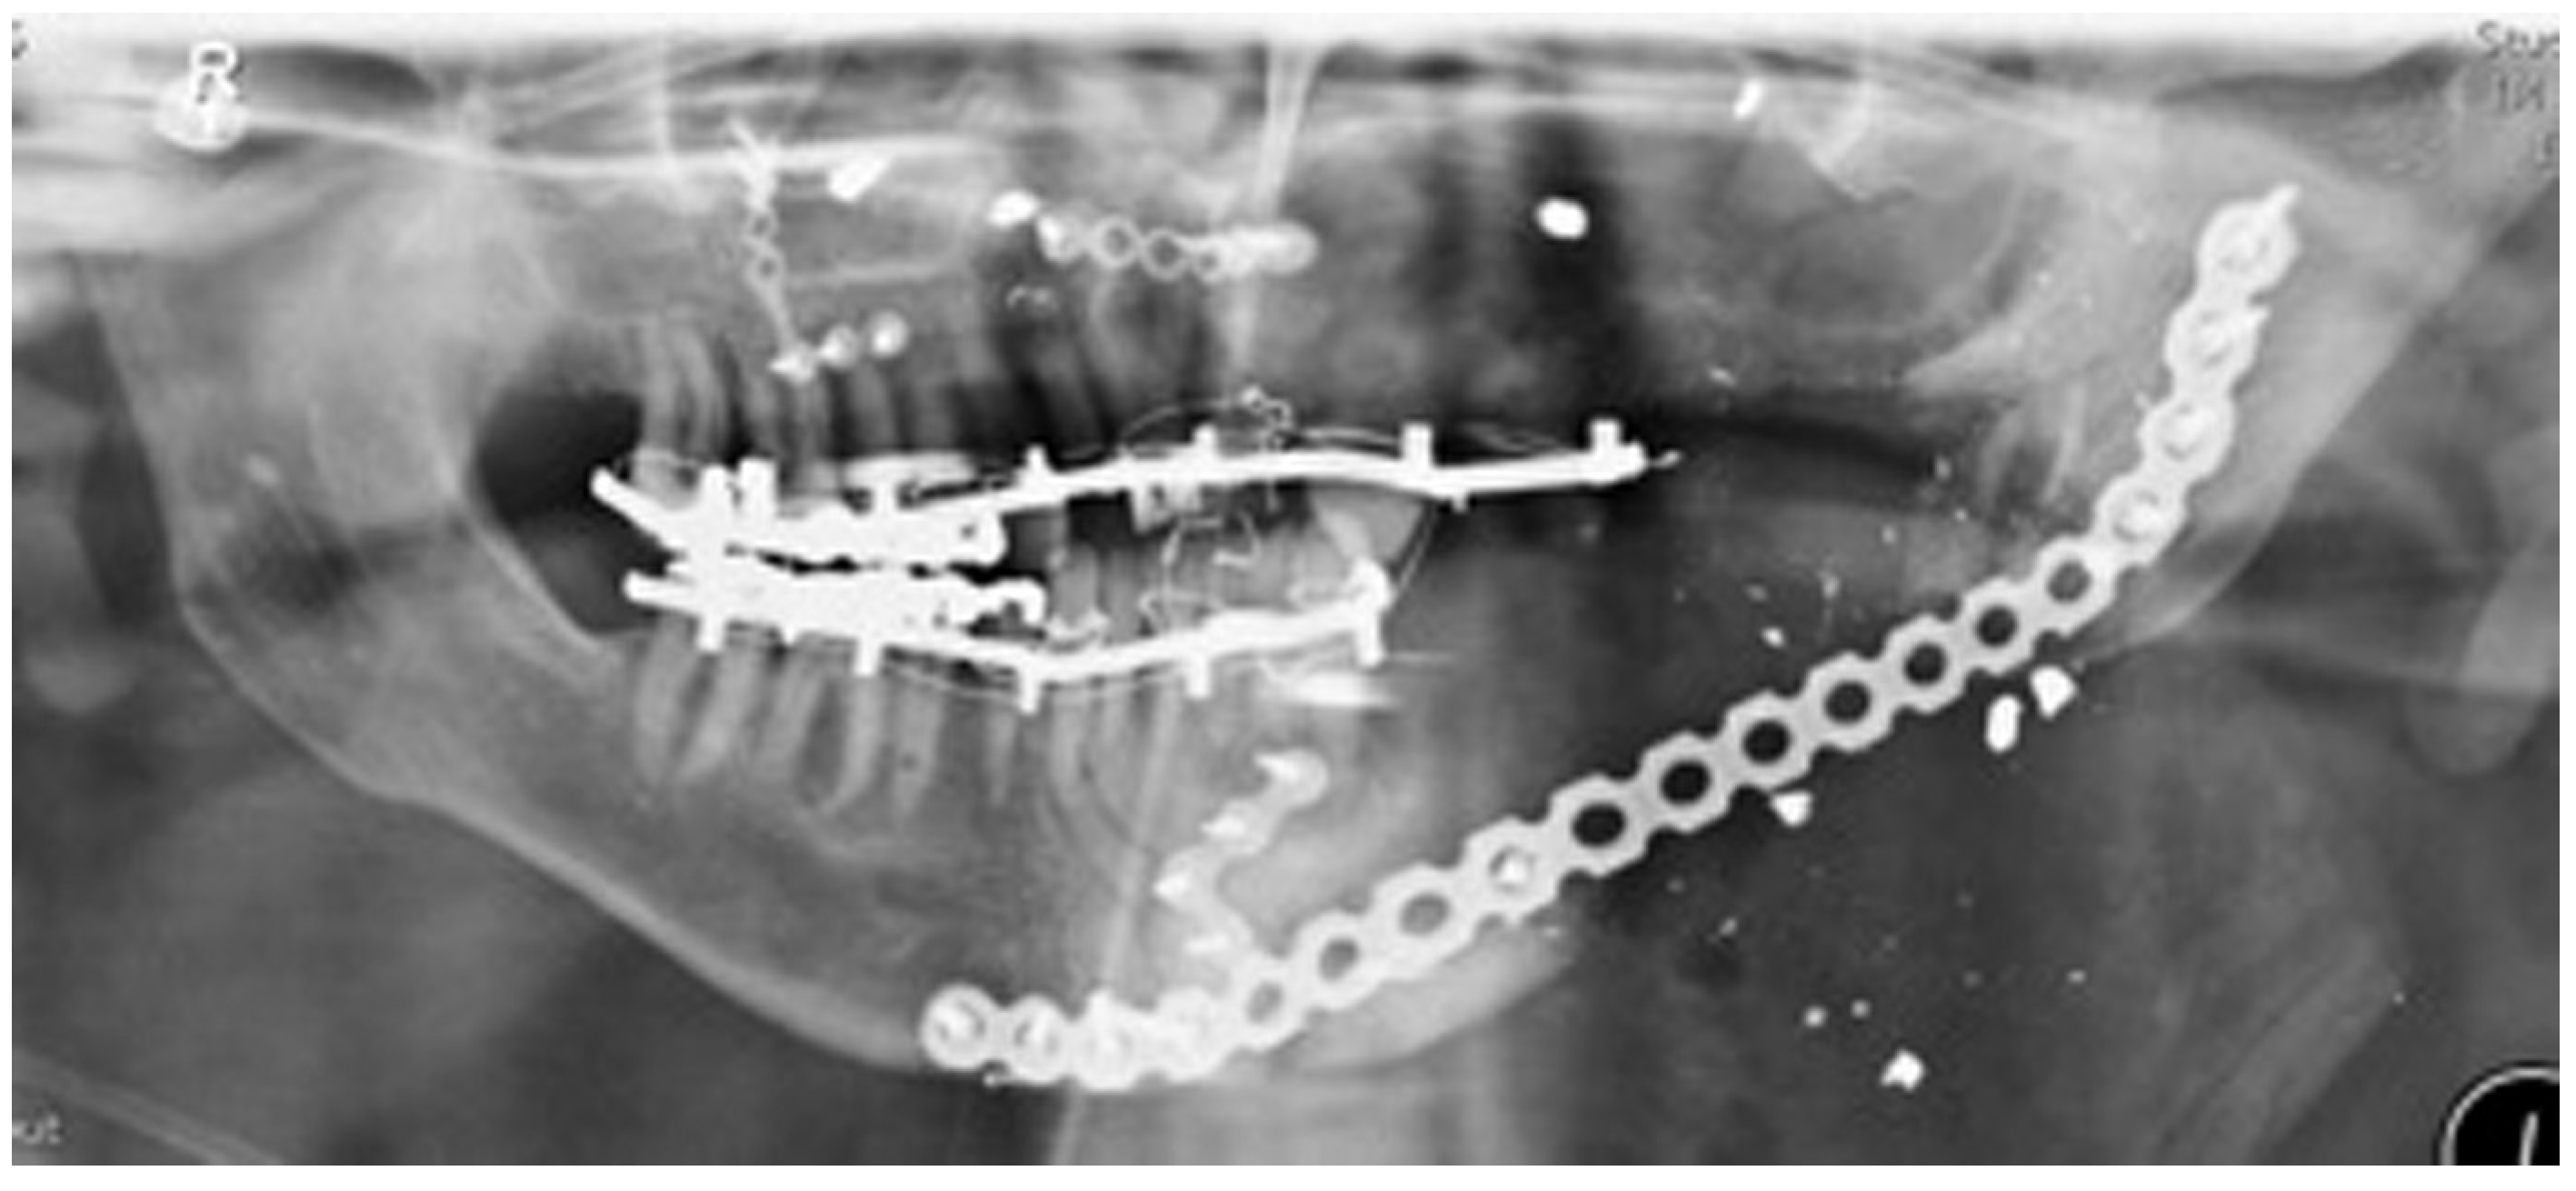

Figure 10.

Stage 1 surgery. Orthopantomography (OPT) to show locking plate to maintain the position of bony fragments whilst oral mucosa is healing in gun shot wound case.